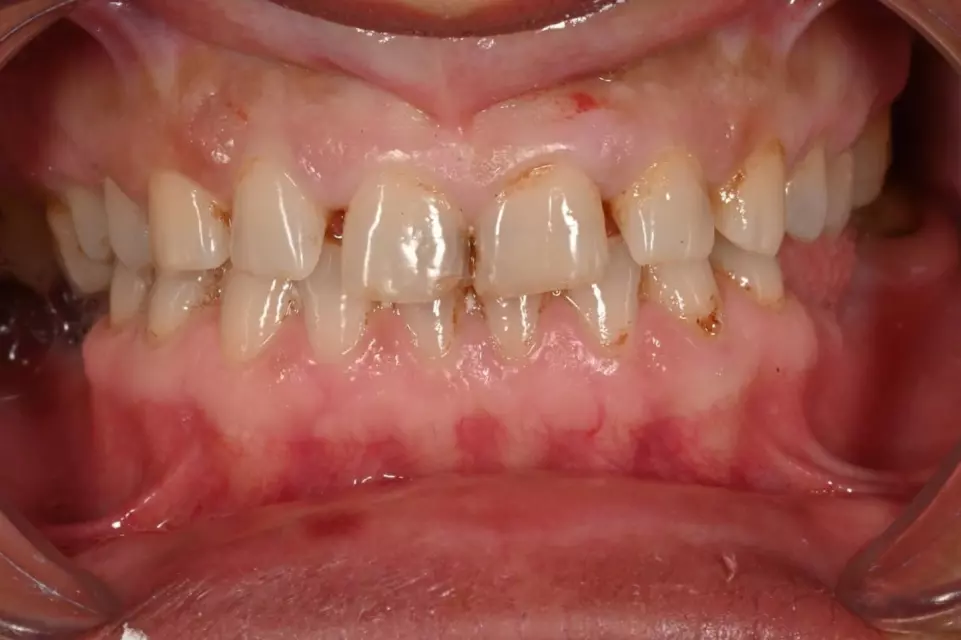

Ortodoncë: Drejtim i dhëmbëve dhe përmirësim i përtypjes me aparate fikse ose mobile bashkëkohore.